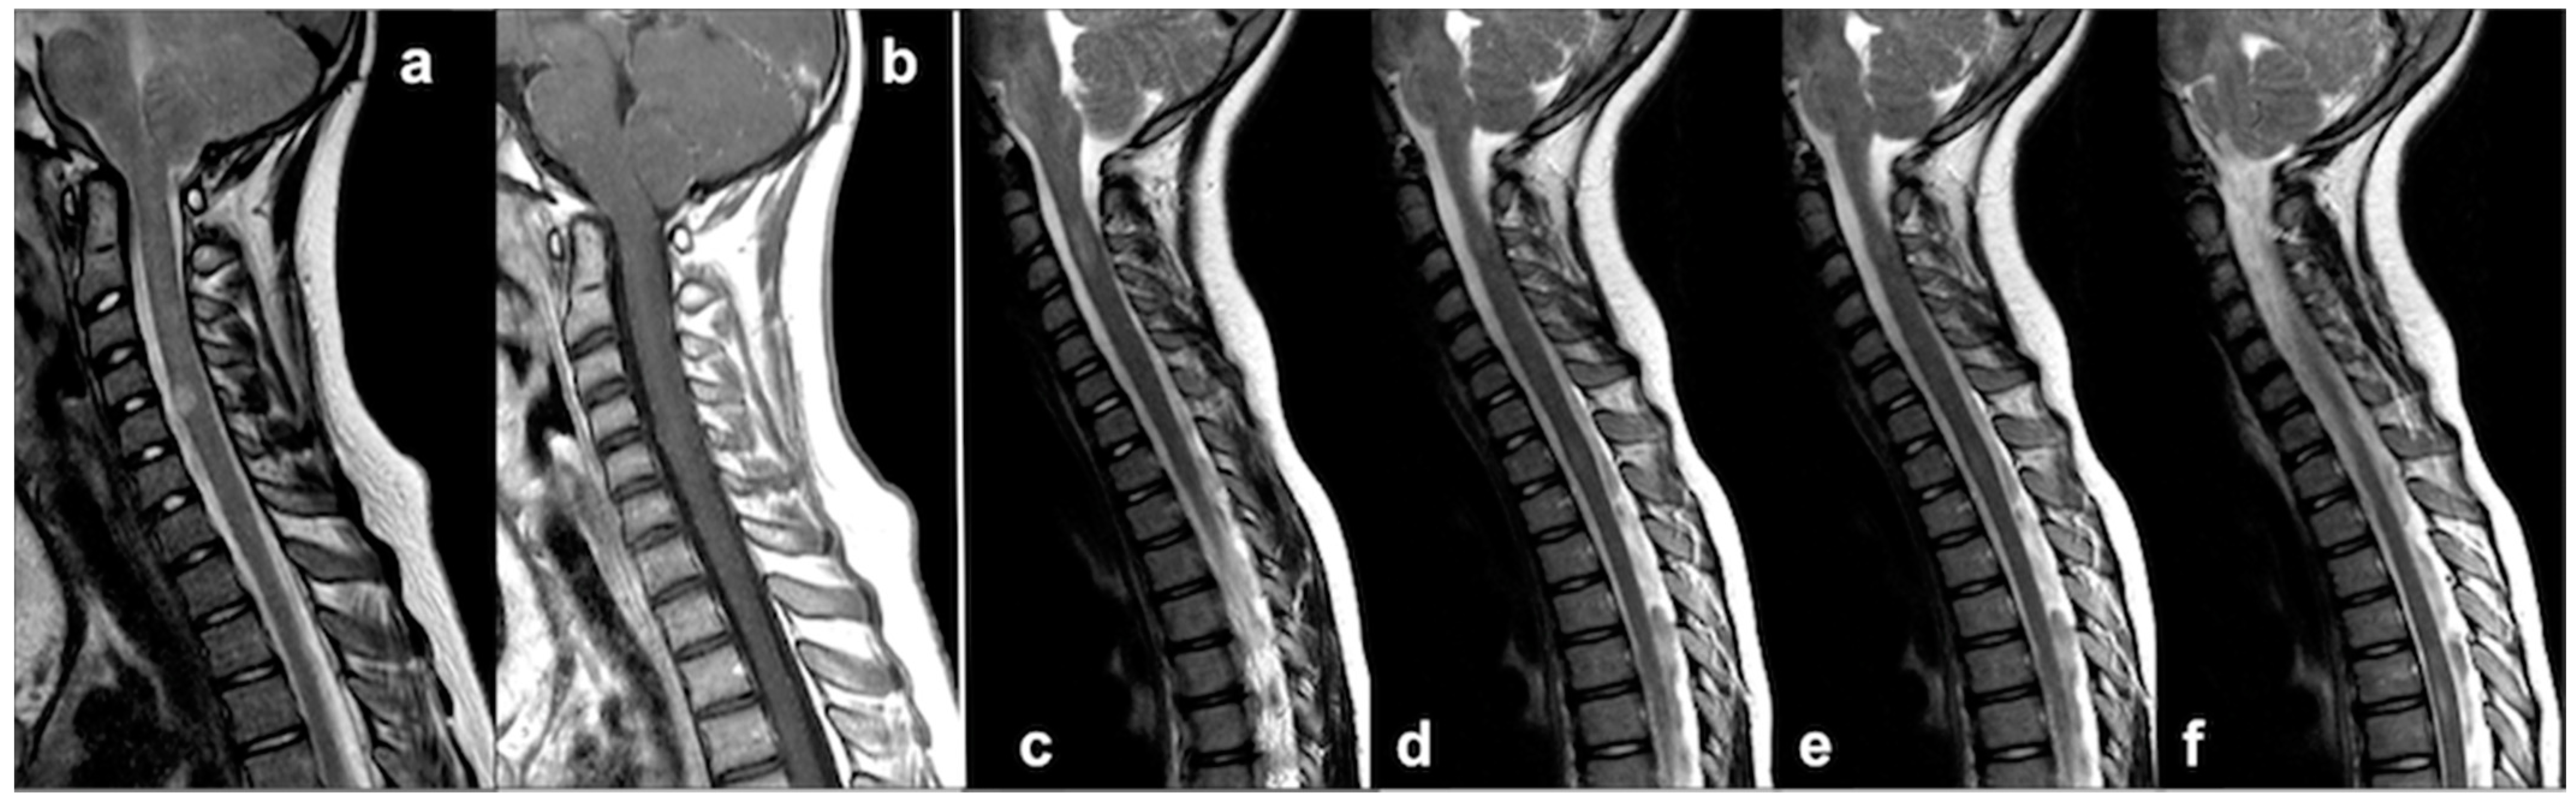

4.1. Medullary UBOs: A Stumbling Block to Neuroimaging

4.2. Dural Ectasia, Meningocele and Spinal Deformity: An Etiopathological Continuum

4.3. Chiari Malformation and Syrinx